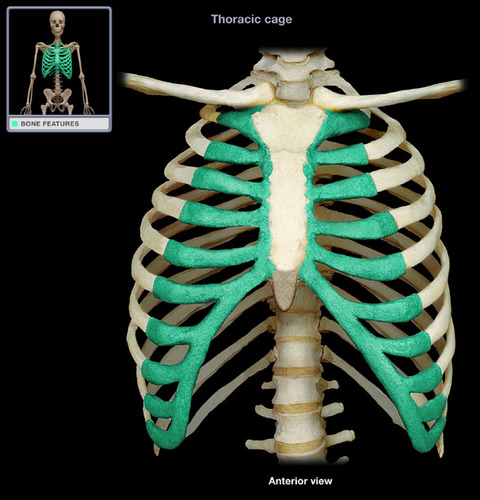

True ribs

7 pairs

False ribs

5 pairs

vertebrochondral ribs

floating ribs

costal cartilage

sterum

Sternum body

sternum manubrium

sternum xiphoid process